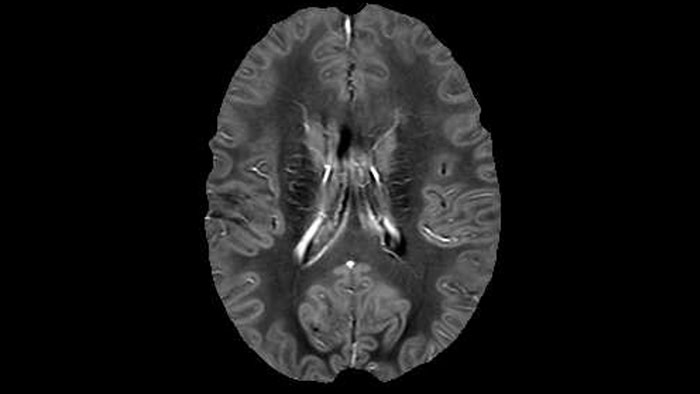

He says the accelerated scanning is achieved via the use of Compressed SENSE and MultiBand SENSE. “We can use Compressed SENSE acceleration factors of about 10 on a 3D FLAIR for instance, which is quite remarkable compared with what we saw with the Achieva. With 3D FLAIR, we can push the spatial resolution to 0.3 cubic mm and it works. Previously, our 3D FLAIR scans lasted about 8 minutes, but now with Elition they are five minutes. The SNR is also visibly better. Our SWI and QSM scans look fantastic. Also, since a lot of neuroimaging is EPI based, using the MultiBand SENSE technique can increase temporal resolution and make it possible to run complicated DTI scans relatively quickly.”

Juxtacortical MS lesion elition

Sagittal 3D FLAIR with 0.3 mm3 voxel volume acquired in 5:12 min. using Compressed SENSE showing a (juxta)cortical MS lesion.